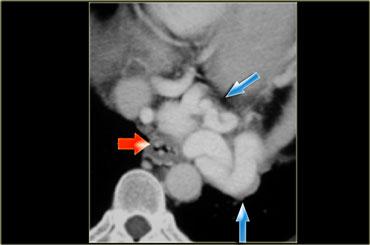

Bên trái là hình ảnh CT của bệnh nhân có giãn tĩnh mạch thực quản hướng lên (Uphill varices) lớn thứ phát do xơ gan kèm tăng áp lực tĩnh mạch cửa.

Bên trái là hình ảnh CT của bệnh nhân có giãn tĩnh mạch thực quản hướng lên (Uphill varices).

TRÁI: Giãn tĩnh mạch sau tim dạng khối (mũi tên). PHẢI: Chụp thực quản cản quang cho thấy giãn tĩnh mạch (mũi tên)

Giãn tĩnh mạch thực quản hướng lên (Uphill varices) có thể có dạng khối như trong trường hợp minh họa bên trái.

Hình CT cho thấy giãn tĩnh mạch trung thất và thực quản dạng khối (mũi tên).

Phim chụp thực quản cản quang cho thấy các khuyết đọng thuốc không hằng định (mũi tên xanh dương) do giãn tĩnh mạch hướng xuống ở thực quản trên.

CT cho thấy giãn tĩnh mạch thực quản (mũi tên đỏ) và trung thất.